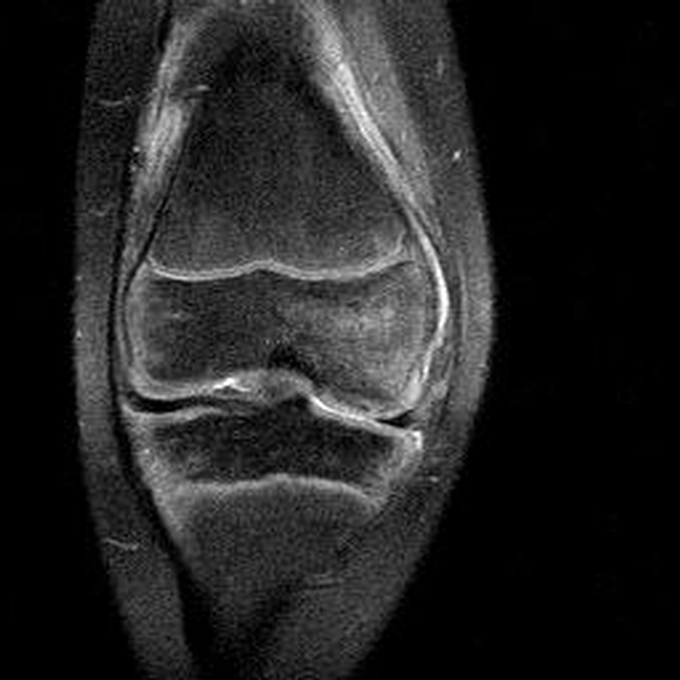

Haemophiliearthropathie bei Haemophilie A.

Arthropathia ARC123 Haemophiliearthropathie bei Haemophilie A.

MRT (high)